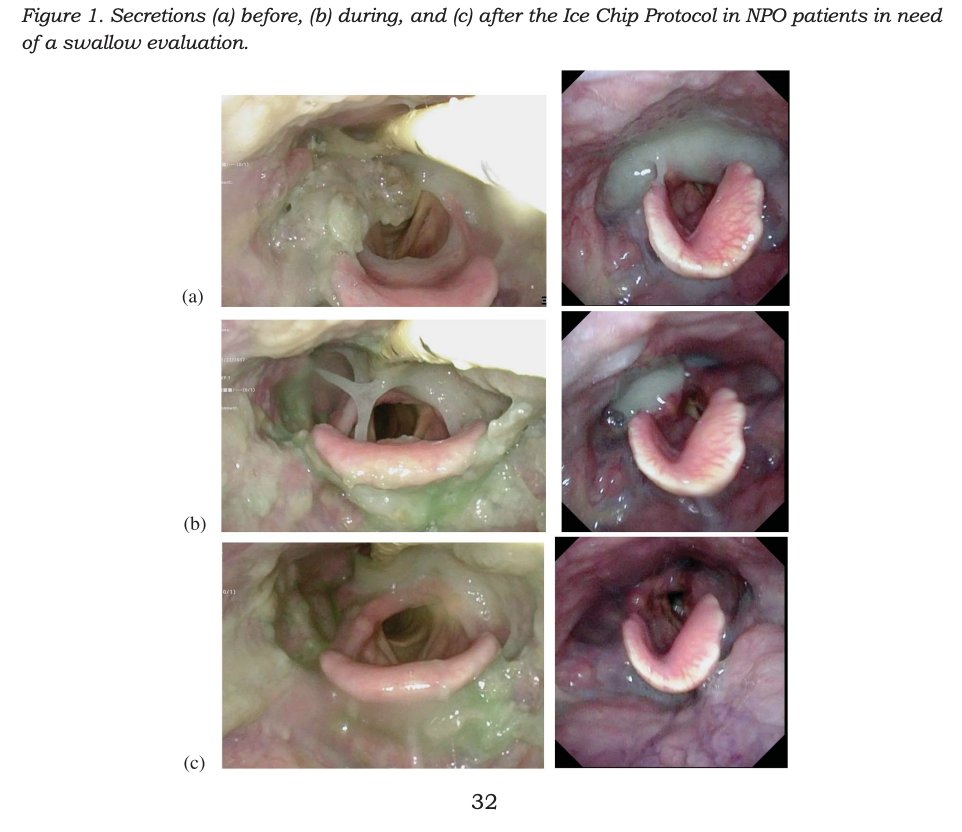

20/#365papers - Stolen from Elly Sampson when she was on her #365papers journey! Because honestly, this image lives in my head rent free everytime I consider putting someone NBM. This is the impact of an ice chip protocol on improving secretions. web.s.ebscohost.com/ehost/pdfviewe…